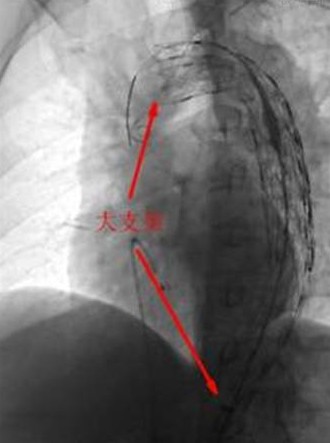

12月2日上午10時(shí),完善各項(xiàng)術(shù)前準(zhǔn)備工作后,患者被送進(jìn)了介入診療中心手術(shù)室。心血管醫(yī)學(xué)中心的專家們迅速為患者實(shí)施了主動(dòng)脈造影術(shù),發(fā)現(xiàn)患者撕裂的主動(dòng)脈竟有兩個(gè)破口!如果不封住這兩個(gè)破口,血流將會(huì)從破口不斷流入撕裂的假腔并導(dǎo)致假腔內(nèi)壓力越來越大,而當(dāng)假腔的壓力達(dá)到一定程度后就有可能完全破裂而導(dǎo)致大出血死亡。因此,如何封住這兩個(gè)破口就成了挽救該患者生命的主要目標(biāo)。以前完成此目標(biāo)必須進(jìn)行開胸手術(shù),將一種人造的血管縫合在夾層的內(nèi)表面從而堵住破口。而心血管醫(yī)學(xué)中心的專家們采用當(dāng)今最先進(jìn)的技術(shù),甚至不需股動(dòng)脈切開,僅僅在大腿根部的股動(dòng)脈打一個(gè)小孔即完成了這一高難度的手術(shù)!他們通過這一小孔建立了一個(gè)輸送通道,并順著這一通道先后將兩個(gè)大覆膜支架由遠(yuǎn)及近釋放到患者撕裂的主動(dòng)脈內(nèi),并牢牢地封住了兩個(gè)撕裂的破口,整個(gè)手術(shù)過程不到2個(gè)小時(shí)!該手術(shù)的成功,標(biāo)志著我市心臟大血管疾病的診療技術(shù)水平又邁上了一個(gè)新的臺(tái)階!